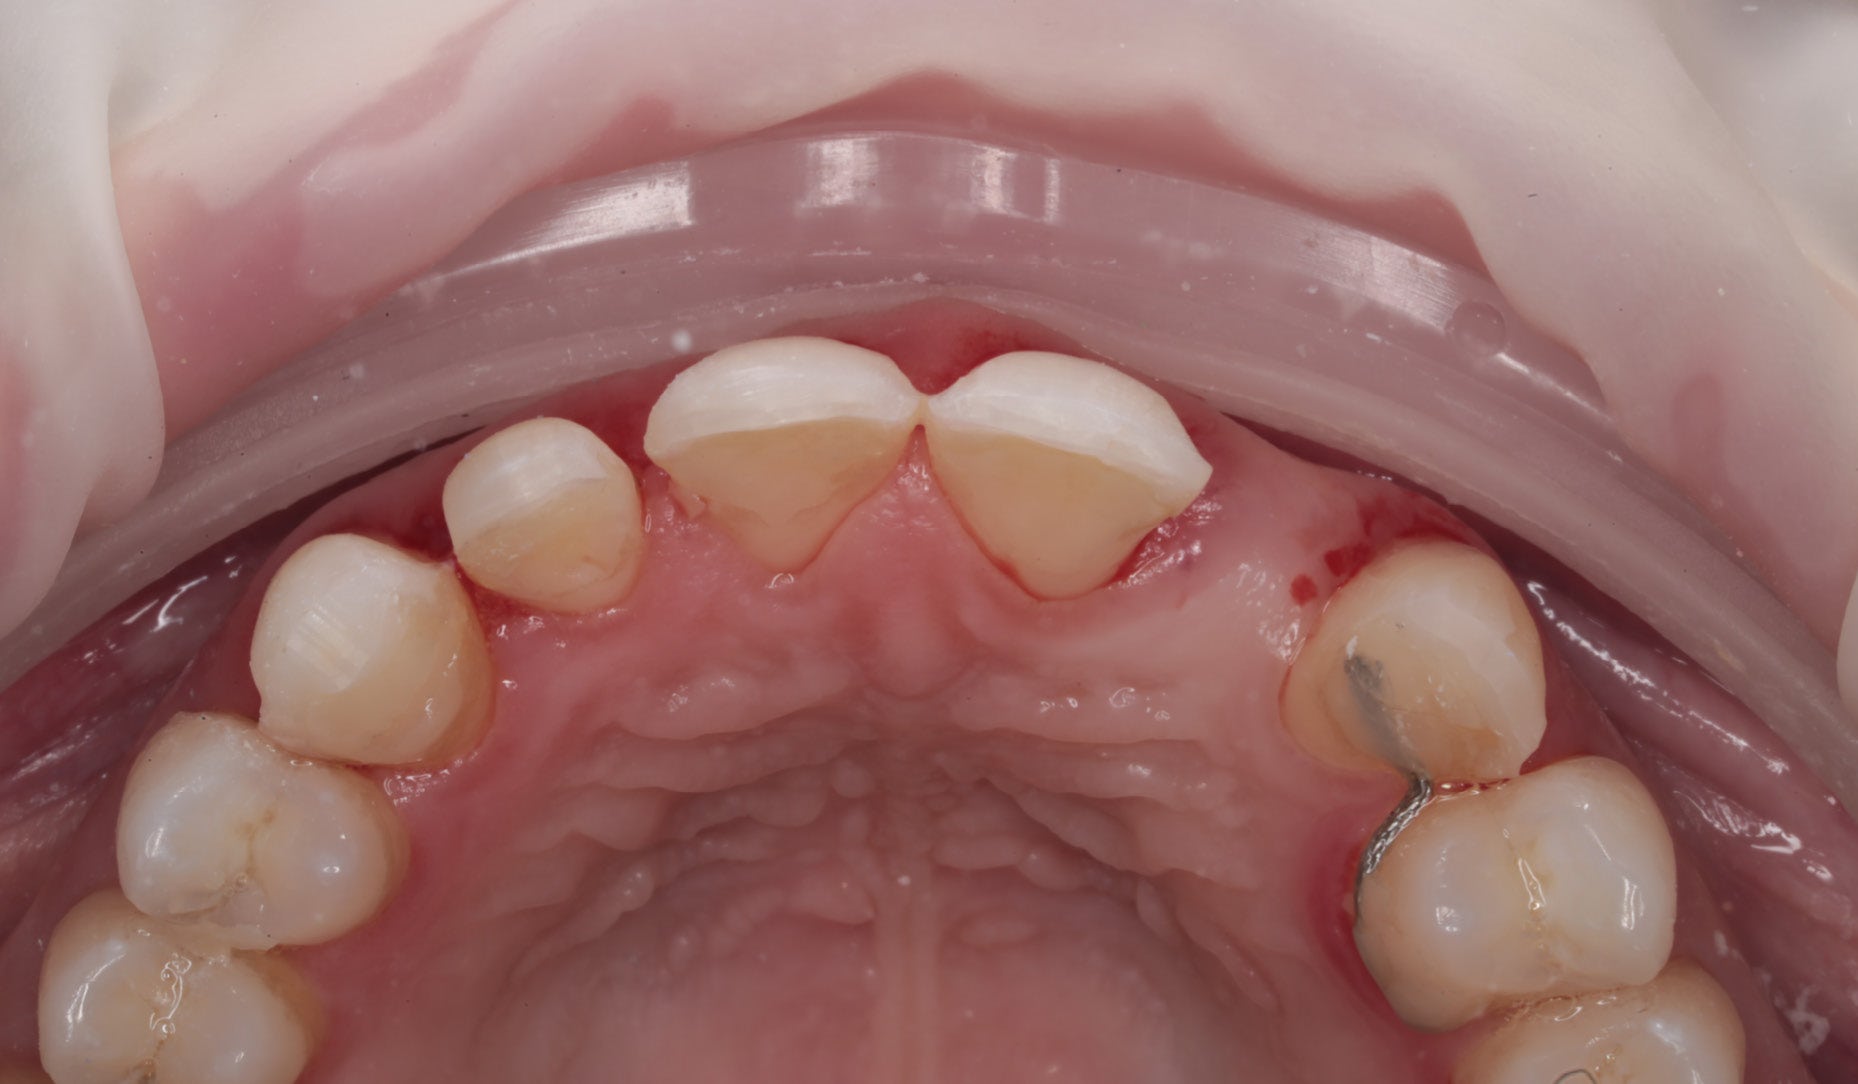

Clinical Cases, Labside Two high-strength ceramics, one micro-layering system Case by DT Andreas Chatzimpatzakis AESTHETIC AND EFFICIENT SMILE MAKEOVER Most patients asking for a smile makeover desire custom solutions rather than an off-the-peg smile: Individual tooth shapes that fit their face and their character, an internal play of colours that matches their age and natural dentition. Modern dental materials allow us to deliver what they demand in many situations – usually at a reasonable price. For a long time, however, we have been facing challenges when combining cosmetic and medically indicated treatment – e.g. a smile makeover including the rehabilitation of a missing lateral incisor. A straightforward solution – using lithium disilicate veneers alongside a zirconia cantilever bridge, both finished with their respective porcelain systems – would have been complicated by potential differences in the final appearance. With CERABIEN™ MiLai (Kuraray Noritake Dental Inc.), a set of internal stains and porcelains designed for micro-layering, the situation is different: Suitable for micro-layering on zirconia and lithium disilicate, it supports its user ideally in creating a harmonious smile even when the two framework materials are combined. A NEW CUSTOM SMILE The following patient case is a perfect example: A female patient with a missing lateral incisor, multiple visible composite restorations in the anterior region and an enamel fracture at her incisal edge desired a smile makeover. The selected materials were Amber Press LT (HASS), shade A1, for four veneers on the central incisors and the left lateral incisor and canine (teeth # 11, 21, 22 and 23 according to the FDI notation) and KATANA™ Zirconia YML (Kuraray Noritake Dental Inc.), shade A2, for the planned cantilever bridge on the maxillary right canine, replacing the missing lateral incisor (teeth # 12 and 13). Fig. 1. Female patient with a missing maxillary lateral incisor and multiple composite restorations in the anterior area – a smile makeover is desired. Fig. 2. Patient with mock-up. Fig. 3. Minimally invasive preparation through the mock-up, which takes into account the minimum space required for the planned materials and restorations. Fig. 4. Teeth prepared for the all-ceramic restorations. Fig. 5. Occlusal view of the maxillary teeth after tooth preparation. Fig. 6. Full-contour veneers and cantilever bridge on the model. Fig. 7. Restorations after a cutback limited to the vestibular and incisal area. Fig. 8. CERABIEN™ MiLai LT1 is applied to the middle and cervical area of the zirconia cantilever bridge. Fig. 9. CERABIEN™ MiLai Value Liner 2... Fig. 10. … and Value Liner 1 applied to the incisal area of the central and lateral incisor restorations. Fig. 11. CERABIEN™ MiLai porcelain Creamy Enamel mixed with Value Liner 2 (70/30) added to the middle and cervical areas of the four lithium disilicate restorations to increase and control the value. Fig. 12. ... while E2 is added to the incisal area of both canines. Fig. 13. Restorations covered by a layer of Tx ... Fig. 14. ... and LTx. Fig. 15. Appearance of the restorations after the first bake. Fig. 16. Adding translucency and opalescence to the cervical area with LT1 and brightness to the ridges with Creamy Enamel. Fig. 17. Completion of the enamel surface with a cover layer of LTx, which is responsible for a high translucency and opalescence. Fig. 18. Result of the second bake. Fig. 19. Final restorations with a natural self-glaze effect on the model. Fig. 20. Final restorations with a natural self-glaze effect in the patient’s mouth. Fig. 21. Smooth optical integration of the restorations. Fig. 22. Beautiful treatment outcome. CONCLUSION With the described approach and selected materials, it was possible to create restorations with a natural shade, shape and texture. They matched not only the appearance of the remaining natural teeth, but also showed internal consistency across the selected framework materials. The technical procedure was quite straightforward and efficient, while the result speaks for itself. Special thanks to Dr. Kanellos Ioannis for the collaboration on this case and for kindly providing the pre- and post-treatment photographs that complemented it. Dental technician: ANDREAS CHATZIMPATZAKIS Based in Athens, Greece, Andreas Chatzimpatzakis is the founder and director of ACH Dental Laboratory (since 2000), specializing in refractory veneers, lithium disilicate, zirconia, and implant prostheses. He graduated in Dental Technology from the University of West Attica and received advanced training in all-ceramic restorations in Helsinki and Japan under renowned masters including Shigeo Kataoka. Since 2017, he has served as an international trainer for Kuraray–Noritake Dental Inc., delivering lectures and hands-on courses worldwide on advanced ceramic techniques. He has also held roles as Key Opinion Leader for MPF Brush Co., Ambassador for Hass Co., and Editor-in-Chief of Laborama. An active member of the Hellenic Academy of Aesthetic Dentistry, his work and articles have been published in both Greek and international journals. Jan 21, 2026 Dental Technician Kuraray Noritake Prosthodontics Clinical Case Katana Zirconia YML CERABIEN MiLai Prosthetic dentistry Lab Dental Ceramics Cad Cam Discs KATANA Zirconia YML View Product CERABIEN MiLai View Product Subscribe to our Newsletter Join thousands of dental professionals and receive free advice that can help you and your career. We will not spam or share your e-mail.